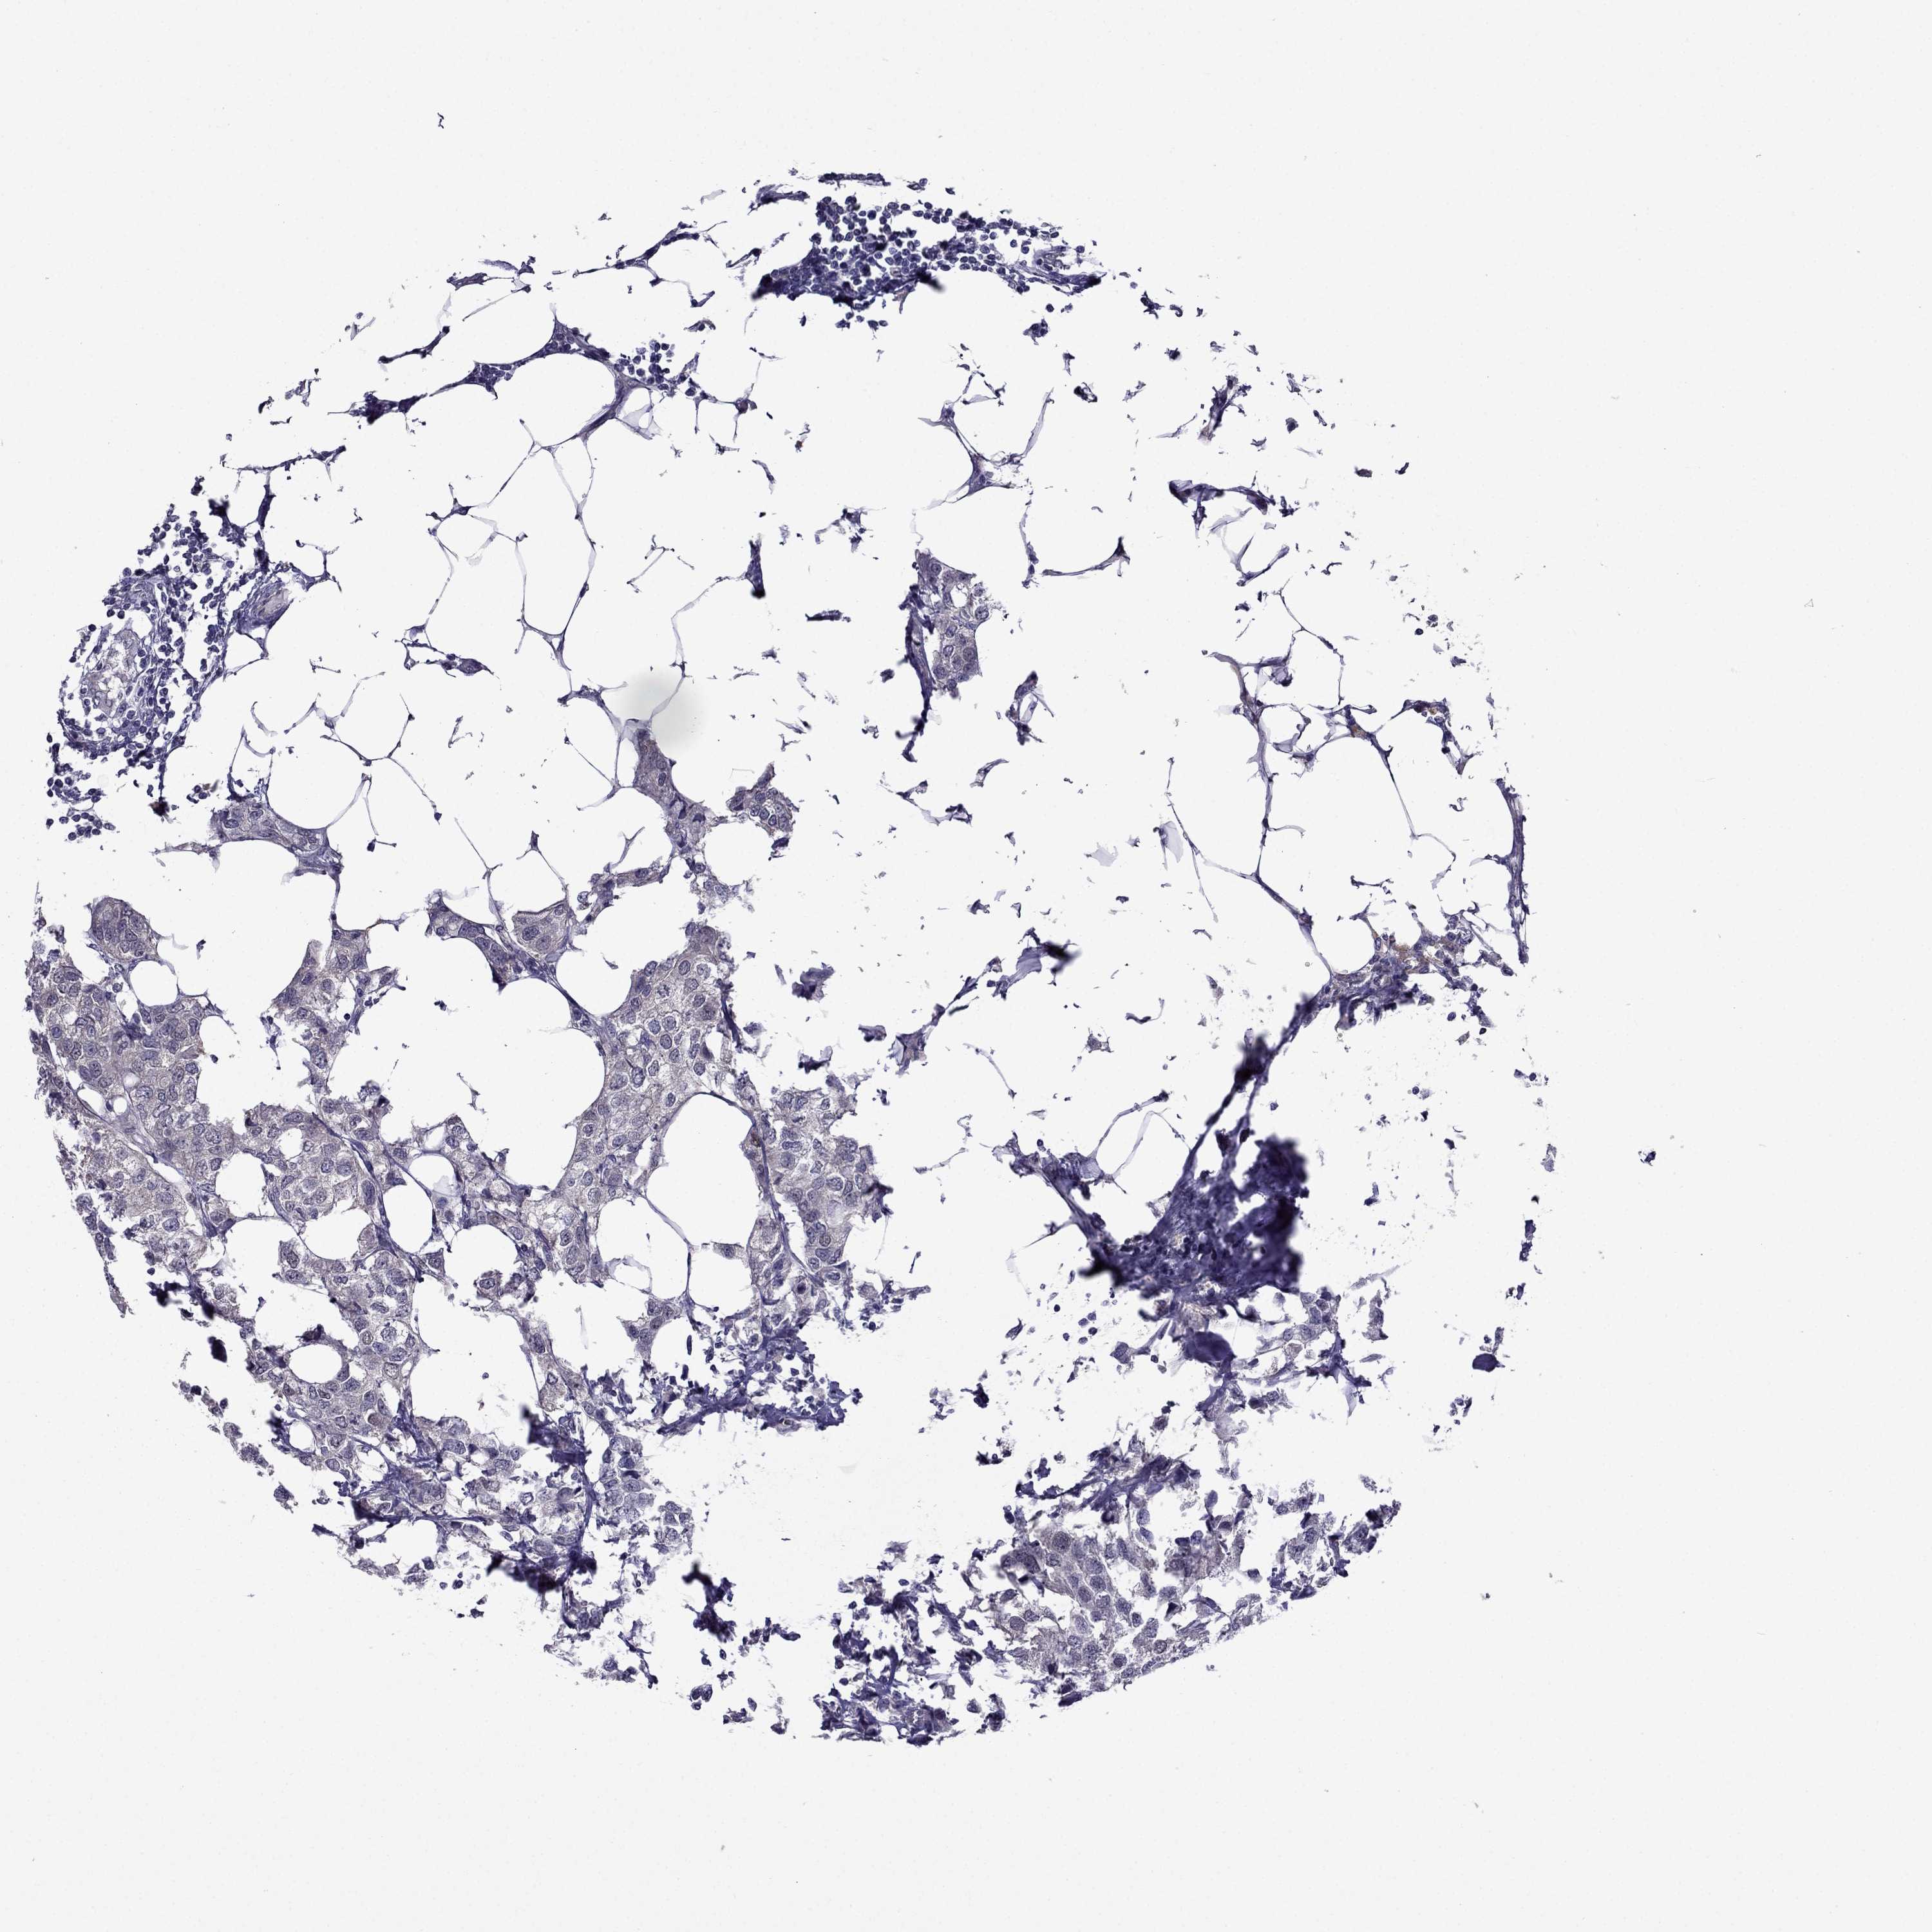

CANCER BREAST CANCER Show tissue menu

BRCA TCGA BRCA VALIDATION PROTEIN EXPRESSION